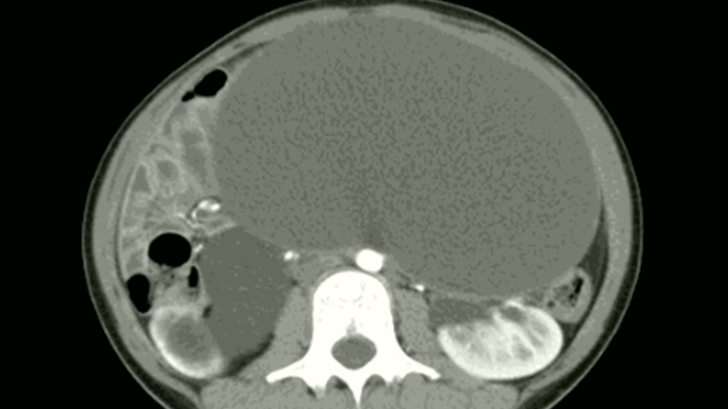

Các bác sĩ Bệnh viện Đa khoa Quảng Ninh ngày 26/1, cho biết kết quả siêu âm, chụp cắt lớp vi tính phát hiện khối u buồng trứng dạng nang chiếm toàn bộ ổ bụng dưới bệnh nhân. Khối u kích thước lớn, dài...